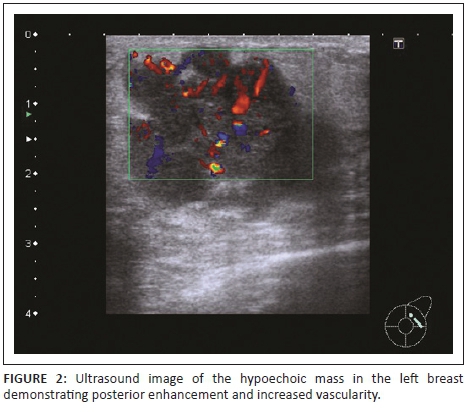

Mammography revealed a large round mass in the superolateral quadrant of the left breast (Figure 1). It had obscured margins, and no calcifications were noted within the mass. Ultrasound showed a heterogeneous mass with increased vascularity and discrete margins measuring 36 mm × 24 mm (Figure 2). There were pathological intramammary and axillary lymph nodes present. An ultrasound-guided core biopsy of the breast mass was performed using a 14-gauge needle. The lower back mass was also biopsied.